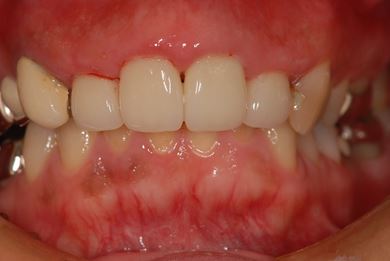

セラミックの症例写真 SHINBI

| 性別/年齢 | 女性 / 41歳 | ||||||||||||||||||||||||||||||||

| 主訴 | 歯が欠けたので、セラミック治療をお願いしたい。 | ||||||||||||||||||||||||||||||||

| 治療方針 | セラミック治療にて、審美的回復を行う。 | ||||||||||||||||||||||||||||||||

| 治療内容 | エンプレスオールセラミッククラウン4本(オールセラミック用土台4本) | ||||||||||||||||||||||||||||||||

| 総治療費 | 408,000円 | ||||||||||||||||||||||||||||||||

| 治療期間 | 4ヶ月 |